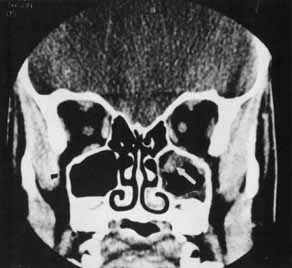

Orbital emphysema results from air forced from the sinus into the orbit. This condition can occur with nose blowing or when orbital fat functions as a ball-valve over the fracture site.53 Emphysema of the soft tissue is appreciated by crepitus that can be palpated in the inflated eyelids. When the orbital septum remains intact, air is confined in the orbital space and can result in proptosis or reduction in motility (Fig. 12). Elevation of intraocular and intraorbital pressure can potentially compromise the retinal or posterior ciliary vasculature. Vision loss from this mechanism has been described,50,54,55 and this loss is considered an ophthalmic emergency. Intervention may include aspiration of air from an accessible site, such as the conjunctiva,50 or lateral canthotomy, with or without cantholysis, to decompress the orbit.52,54 More often, the condition is not sight-threatening and is self-limited. To avoid further inflation, the patient should be advised to not blow the nose or generate a Valsalva maneuver.

Fig. 12 In this patient (A) with right medial wall and tripod fracture, the mass effect of orbital air (B) (arrow) causes exophthalmos and contributes to hypophthalmos.